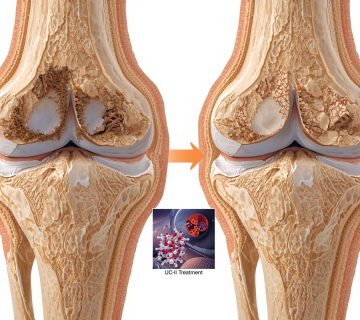

ایمنی و اثربخشی کلاژن آندینیچرد تایپ 2 (UC-II) در درمان استئوآرتریت زانو

استئوآرتریت (OA)یا آرتروز یکی از شایعترین انواع آرتریت است که میلیونها نفر را در سراسر جهان تحت تأثیر قرار میدهد و باعث درد، سفتی و کاهش کیفیت زندگی میشود. درمانهای فعلی عمدتاً علائم را تسکین میدهند و بیماری را معکوس نمیکنند. کلاژن آندینیچرد تایپ 2 (UC-II) که از جناغ سینه مرغ استخراج میشود، در مطالعات قبلی نشان داده است که میتواند در درمان آرتریت روماتوئید (RA) مؤثر باشد. این مطالعه به بررسی ایمنی و اثربخشی UC-II در مقایسه با ترکیب گلوکوزامین و کندرویتین (G+C) در درمان آرتروز زانو پرداخته است.

مصرف روزانه 40 میلیگرم UC-II به مدت 90 روز منجر به بهبود معنادار در درد، سفتی و عملکرد فیزیکی بیماران مبتلا به آرتروز زانو شد و اثربخشی آن بهطور قابل توجهی بالاتر از ترکیب گلوکوزامین و کندرویتین بود. همچنین، UC-II ایمنی خوبی داشت و عوارض جانبی کمتری نشان داد. این مطالعه نشان میدهد که UC-II میتواند بهعنوان یک گزینه درمانی مؤثر و ایمن برای بیماران مبتلا به آرتروز زانو مورد استفاده قرار گیرد.

- درمان آرتروز: UC-II میتواند بهعنوان یک مکمل طبیعی برای کاهش درد و بهبود عملکرد مفاصل در بیماران مبتلا به آرتروز استفاده شود.